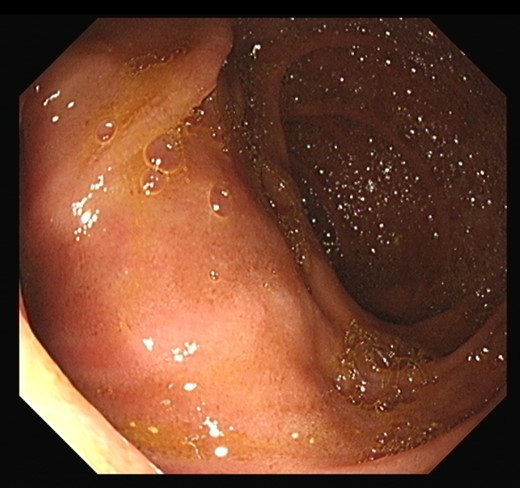

The patient underwent an MRCP which demonstrated mild distension of the gallbladder with several calculi. There was intra- and extra-hepatic biliary dilatation to the level of the ampulla. A very large fluid and air filled periampullary duodenal diverticulum measuring ~8 cm in the long axis was also noted (Figs 1–3). This finding was unchanged compared to a CT study from 6 months previously. The CBD was dilated to the level of this diverticulum and the cause of the patient’s biliary dilatation and obstruction. Interestingly, an unusual appearance to the kidneys was recorded with multiple microcystic changes in both kidneys, which is typically reported in patients with lithium induced renal disease. A gastroduodenoscopy revealed a large periduodenal diverticulum in D2 (Fig. 4).

Magnetic resonance imaging with a giant duodenal diverticulum.